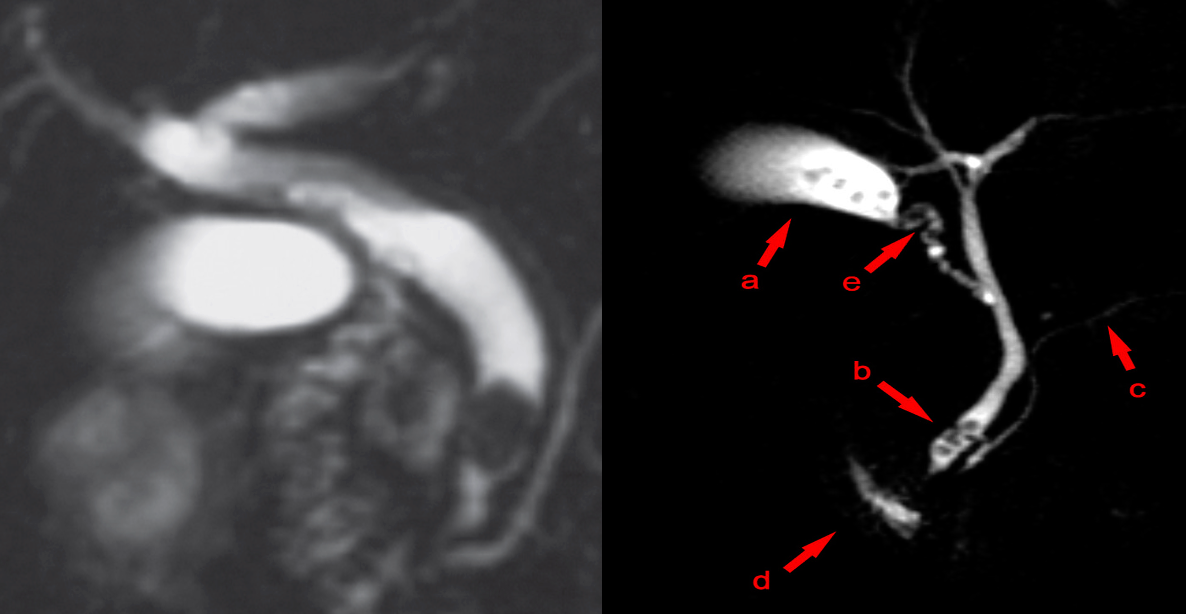

Magnetic resonance cholangiopancreatography (MRCP):

MRCP showing cholelithiasis and Choledocholithiasis ((1st image normal))

Filling defects (i.e., the dark spots or areas that have not taken up the contrast) are visible within the gallbladder (a), the cystic duct (e), and the common bile duct (b). c: pancreatic duct; d: duodenum

These features are diagnostic of cholelithiasis complicated by choledocholithiasis.